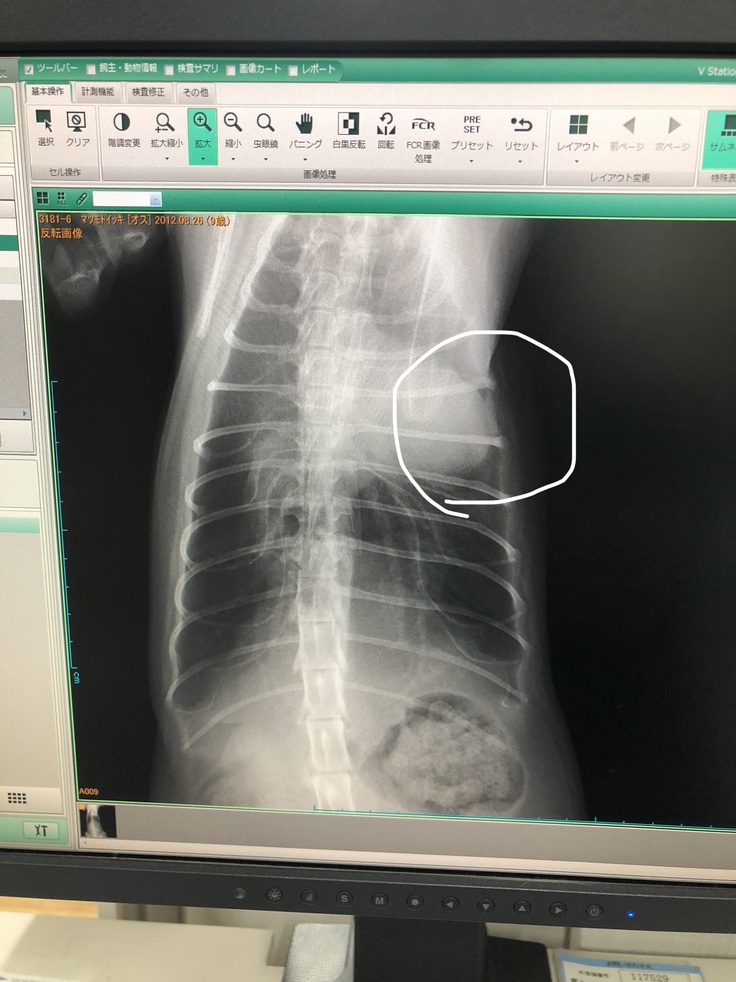

急ぎ夕方からの診察に予約を入れようと準備中、呼吸困難を起こし、すぐ救急で動物病院へ向かいました。診察して頂いた結果、レントゲン検査では、内臓などには異常は無かったのですが、鼻腔内炎症で器官が狭くなり、呼吸困難になったと診断され、重度のアレルギー性気管支炎との診断を受けました。

(下記写真は入院した時のものです)

この時も、投薬治療と酸素吸入を行いましたが、慢性的な重症と診断され、先生からは「酸素室から出すと、呼吸が安定しないので、入院し、様子を見ましょうと」言われました。

お約束内容が変わってしまう為、誠に申し訳ございません。支援募集の最中、中々良くならないので、別の病院で検査を受ける事にしました。別の病院での検査結果は心臓近くに腫瘍があるとの事で、手術は出来ないと言われ、治療も長期化するとの事でした。これからの治療方針として、6/8から1週間、毎日1回の皮下注射を続け、1週間に1度レントゲンを撮り経過観察をします。

(資料掲載の許可を頂いております)

(別の病院の明細と血液検査結果ですが、病院のご都合により、お名前は伏せさていただきます。ひとつのかがやきでイツキです。)